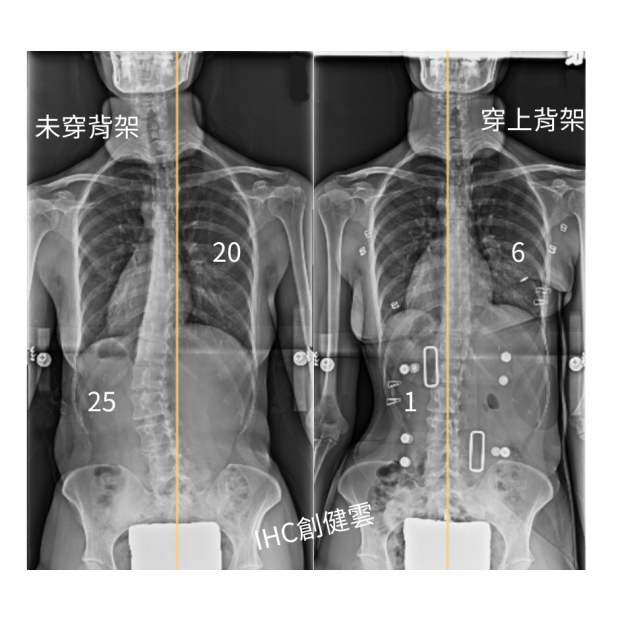

33歲脊椎側彎成年女性,胸彎20度,腰彎25度 穿上背架後立即矯正效果優異

33歲脊椎側彎女性,胸彎20度,腰彎25度,

穿上【施羅斯側彎矯治背架】後,胸彎6度,腰彎1度。

背架的立即矯正效果對成年人來說非常不錯~